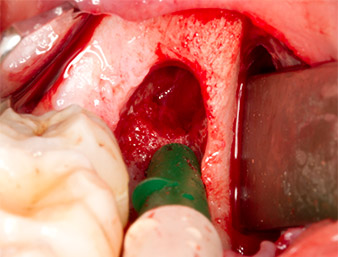

Piezomed B5

Fig. 5 : Une élévation osseuse est pratiquée dans la région de l’alvéole à l'aide d’un instrument piézochirurgical en forme de burin (Piezomed B5). Cet os est utilisé comme matériau d’augmentation autologue après l’extraction du reste radiculaire (cf. Fig. 13 et 14).

Le tissu autogène est extrait à l’aide de la section en forme de racloir de la pièce active de l’insert et conservé dans un soluté physiologique isotonique jusqu’à utilisation ultérieure (cf. Fig. 13).

Pour exposer le reste radiculaire en minimisant le traumatisme causé aux tissus, un autre insert est utilisé (Piezomed S2) qui est principalement indiqué pour la préparation de la fenêtre latérale dans les élévations de plancher sinusien. La boule diamantée est également utilisée pour adoucir les bords osseux tranchants (Fig. 6 et 7). Tous les inserts Piezomed sont utilisés avec le paramétrage par défaut automatique, et sans la fonction Booster.

Piezomed S2

Fig. 6 : Le reste radiculaire est soigneusement exposé à l’aide d’un insert sphérique diamanté (Piezomed S2), les arêtes osseuses sont adoucies.

Reste radiculaire 38

Fig. 7 : Le reste radiculaire 38 (LL8) est bien exposé dans son alvéole en vue de son extraction ultérieure.